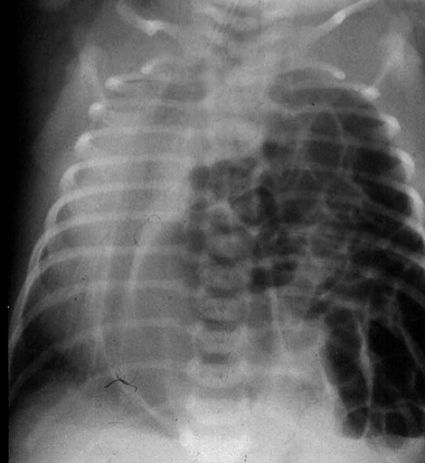

Kongenitalt diafragmabråck [1] drabbar 1 på 2 500–4 000 levande födda barn [2-4]. 90 procent av defekterna finns i den posterolaterala delen av diafragma, s k Bochdalek’s hernia, och i 80 procent av fallen på vänster sida (Figur 1). Av alla neonatala missbildningar är kongenitalt diafragmabråck en av dem som länge förknippats med låg överlevnad, och tillståndet är än i dag en av de största utmaningarna inom barnkirurgin, barnintensivvården och neonatologin [5]. Det beror till stor del på den lunghypoplasi och pulmonella hypertension som ses hos dessa patienter [6, 7].

Av de 184 patienterna behövde 120 intuberas inom sex timmar efter födelsen (Tabell II). Födelsevikt (3,3 ± 0,70 kg) och gestationsålder (38 ± 2,4 veckor) för dessa var desamma som i hela materialet på 184 patienter (3,3 ± 0,66 kg respektive 38 ± 2,4 veckor). Majoriteten av patienterna var pojkar (118 pojkar, 66 flickor), och fördelningen mellan könen var densamma som i riskgruppen som intuberades inom sex timmar. 141 av patienterna hade vänstersidigt bråck, 22 högersidigt och en bilateralt bråck.